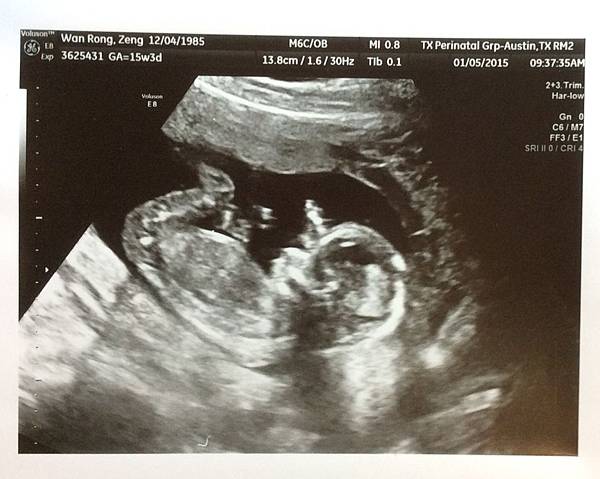

然後她就安排我們做超音波檢查

前後有2位醫生幫我做超音波

都檢查的很仔細

腦部、心臟、腎臟等等 能盡量看清楚的都盡量看(此時14w3d)

2位醫生都說目前為止看起來很正常

1/5已是15w3d

醫生用超音波鎖定好baby的位置